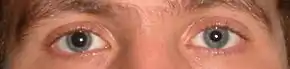

When the pressure within the skull (intracranial pressure, abbreviated ICP) rises too high, it can be deadly.[51] Signs of increased ICP include decreasing level of consciousness, paralysis or weakness on one side of the body, and a blown pupil, one that fails to constrict in response to light or is slow to do so.[51] Cushing's triad, a slow heart rate with high blood pressure and respiratory depression is a classic manifestation of significantly raised ICP.[11] Anisocoria, unequal pupil size, is another sign of serious TBI.[39] Abnormal posturing, a characteristic positioning of the limbs caused by severe diffuse injury or high ICP, is an ominous sign.[11]